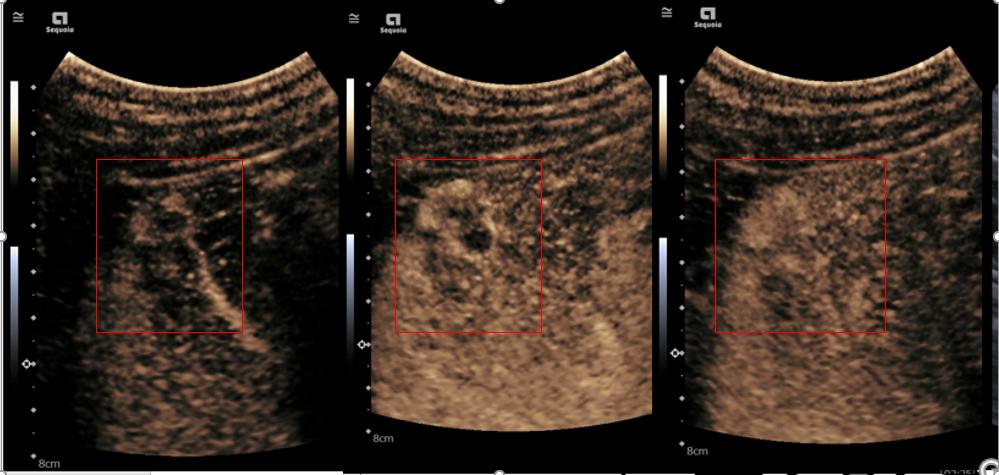

肝脏血管瘤造影图像显示